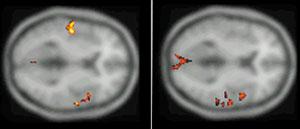

Именно наличие клиники во многом определяет возможности фундаментальных и прикладных исследований ИМЧ. Поэтому прежде всего несколько слов о ней. У нас прекрасные высококвалифицированные доктора и медсестры. Без этого нельзя: ведь мы на переднем крае, и нужна высочайшая квалификация, чтобы выполнять нерутинное, новое. У нас выполняются практически все стандартные манипуляции и наряду с ними и хирургическое лечение эпилепсии и паркинсонизма, проводятся психохирургические операции, в том числе и хирургическое лечение обусловленного героином обсессивно-компульсивного синдрома, знаменитая «пересадка мозга», точнее имплантация фетальной мозговой ткани, лечение магнитости-муляцией мозга, лечение афазии с помощью электростимуляции и многое другое. Накоплен десятилетний опыт клинических обследований с помощью позитронно-эмиссионной томографии. На рисунках приведена малая толика того, что может диагносцировать этот метод томографии. У нас лежат тяжелые больные, и мы стараемся помочь с помощью вышеперечисленных методов даже тогда, когда все остальные попытки были неудачны. Конечно, это удается не всегда. Но безграничных гарантий в лечении людей дать невозможно, а если кто-то дает их, это всегда вызывает очень серьезные сомнения.

Последствия острого нарушения мозгового кровообращения.

Зона, лишенная кровотока, типичной конусообразной формы (красные стрелки), характерной для последствий острого нарушения мозгового кровообращения. Впереди от нее зона снижения кровотока (белая стрелка).

Височная эпилепсия.

Выраженное снижение уровня потребления глюкозы (красные стрелки) в коре левой височной доли, где расположен очаг эпилепсии.

Дифференциальный диагноз опухолей головного мозга.

В зоне поражения (красные стрелки) не накапливается радиофармпрепарат, что исключает опухоль головного мозга.

Злокачественная опухоль головного мозга.

Очерченный очаг резко повышенного неоднородного накопления 11С-метионина в злокачественной опухоли левой височной доли (красные стрелки), которая неотчетливо контурировалась на магнитно-резонансных томограммах.